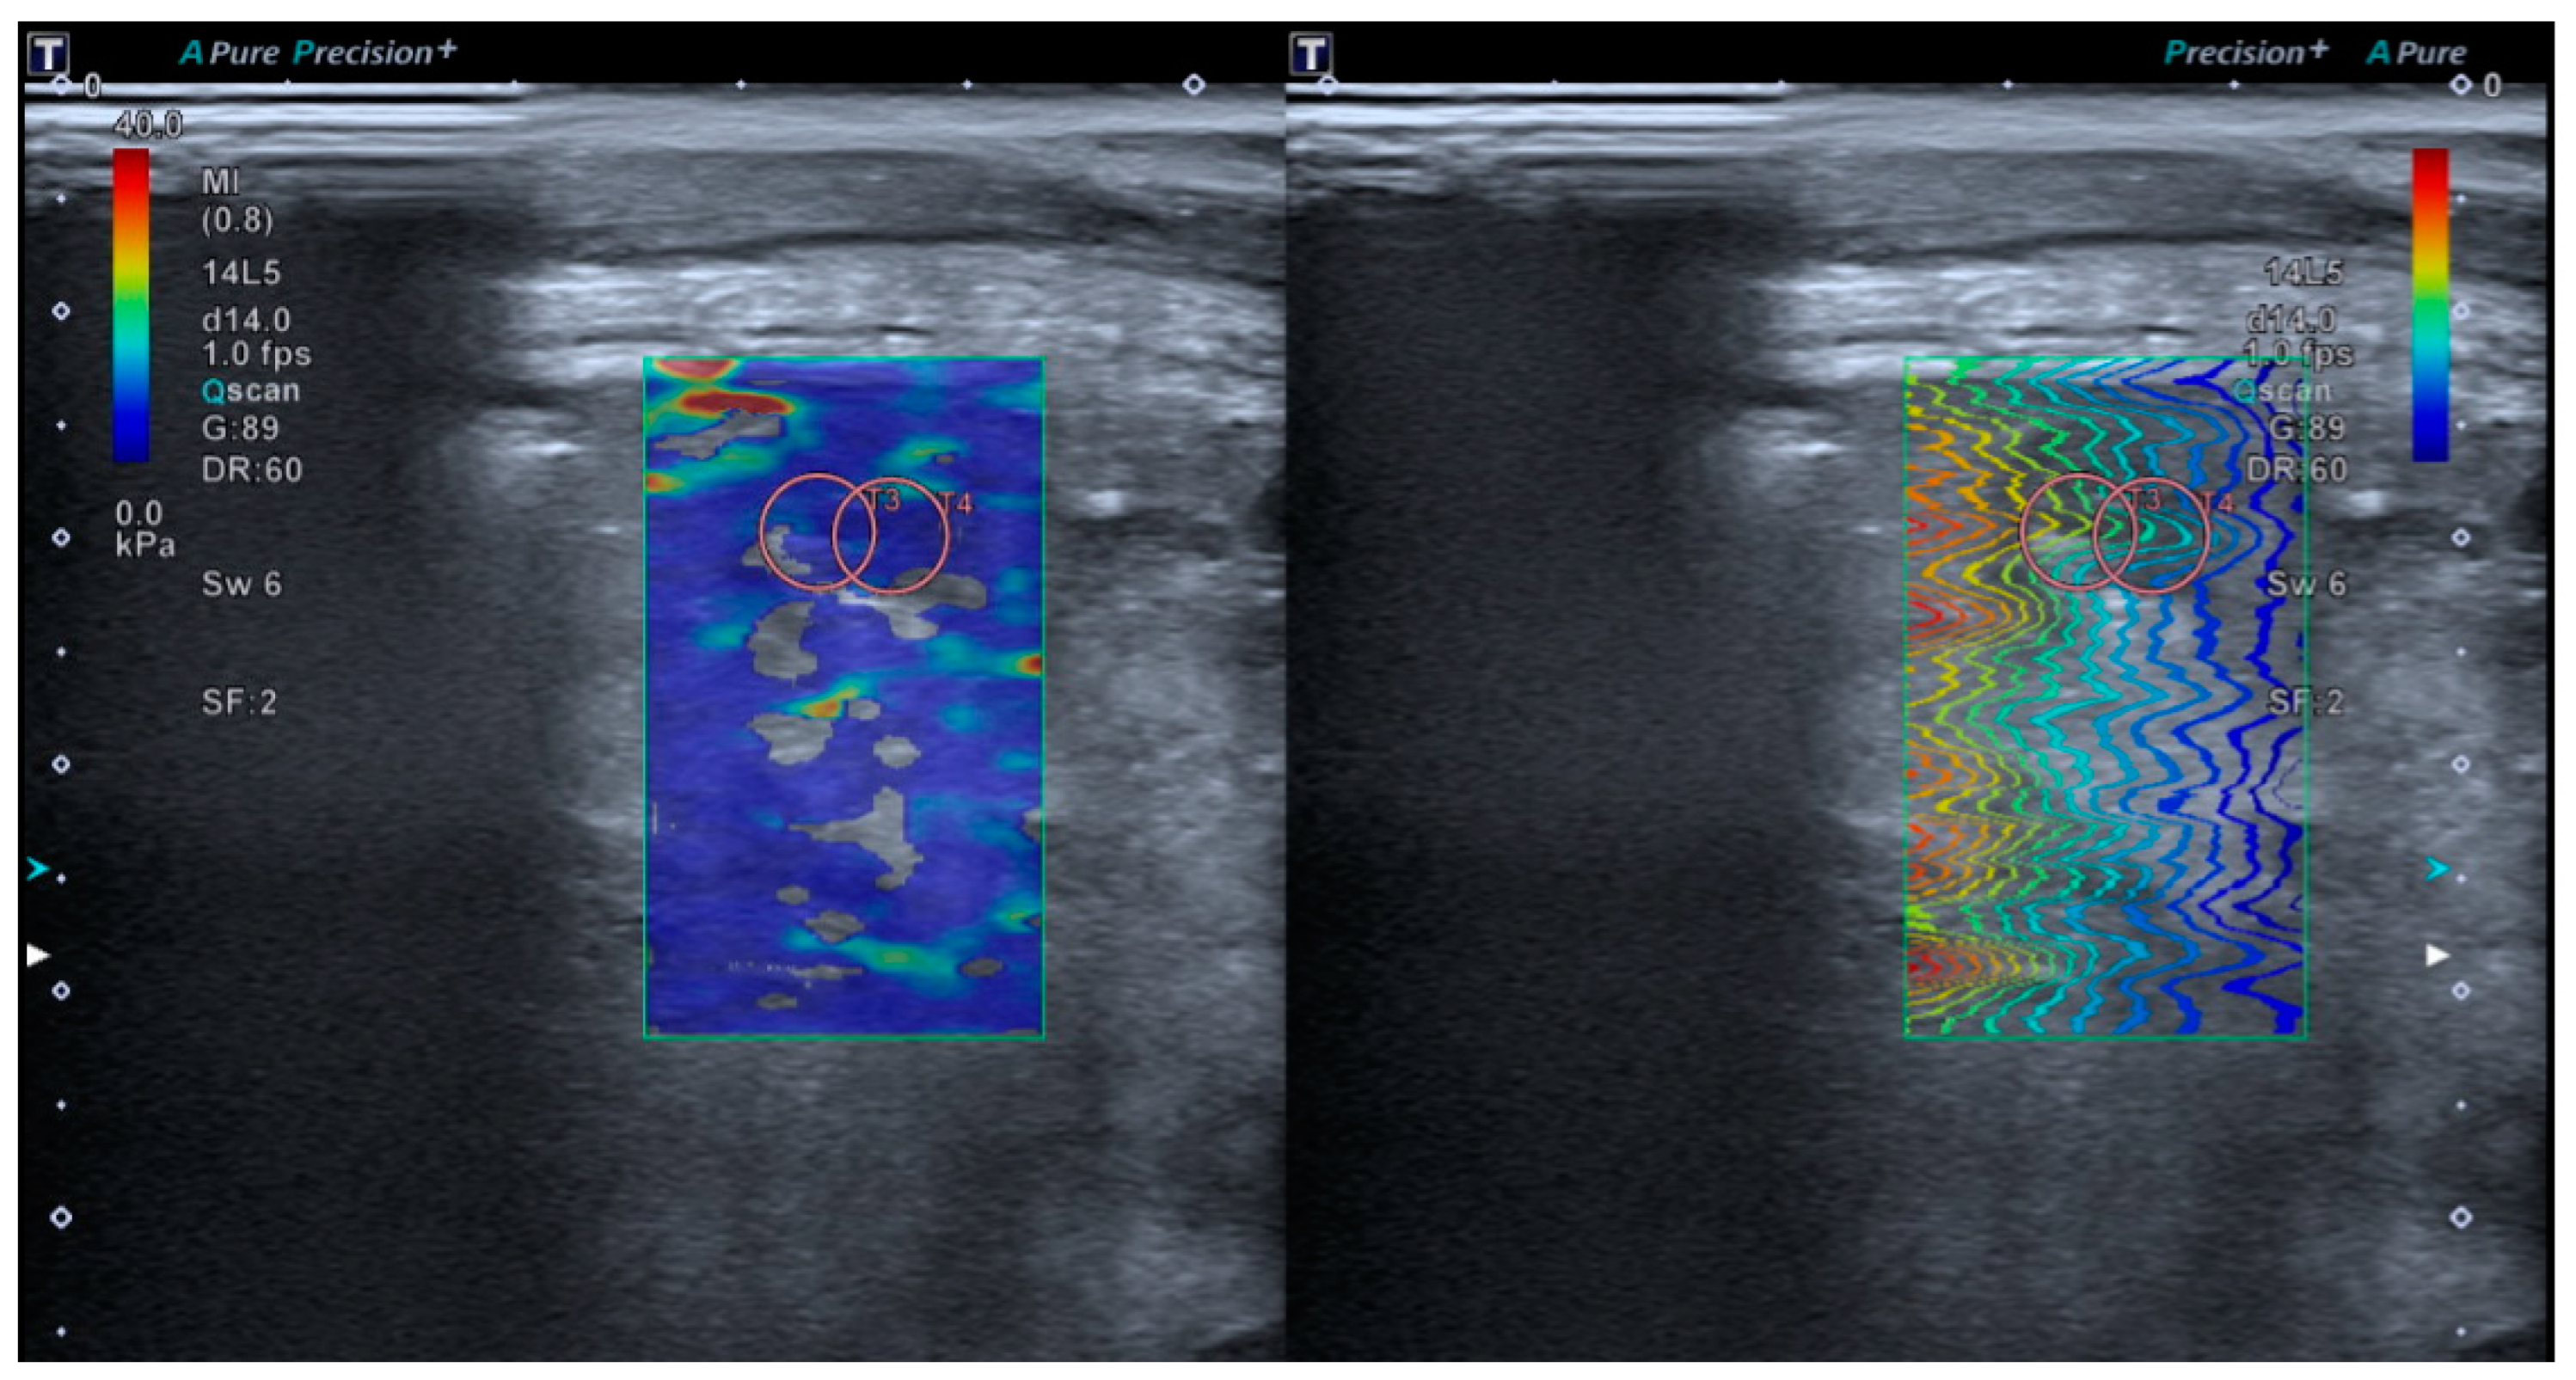

2.4.2. Lung Shear Wave Elastography Acquisition

2.4.3. Superb Microvascular Imaging Acquisition